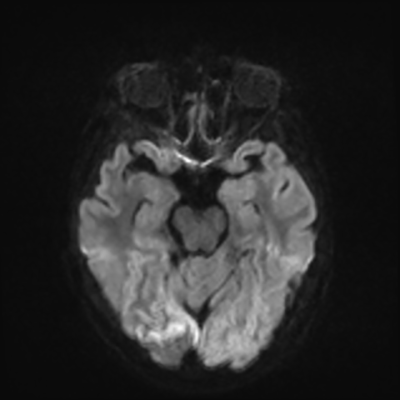

MRI brain (DWI)

You can clearly see diffuse cortical and basal ganglia diffusion restriction, and that of his deep cerebellar nuclei as well. The right occipital lobe abnormalities are a little more prominent, but then you remember that he is known to have had a right occipital stroke weeks ago.